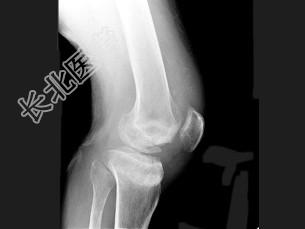

- 单项选择题男,67岁, 脊髓痨患者,右下肢麻木, 右膝关节肿胀,结合图像, 最可能的诊断是 ( )

A、创伤性关节炎

B、退行性骨关节病

C、神经性关节病

D、风湿性关节炎

E、痛风